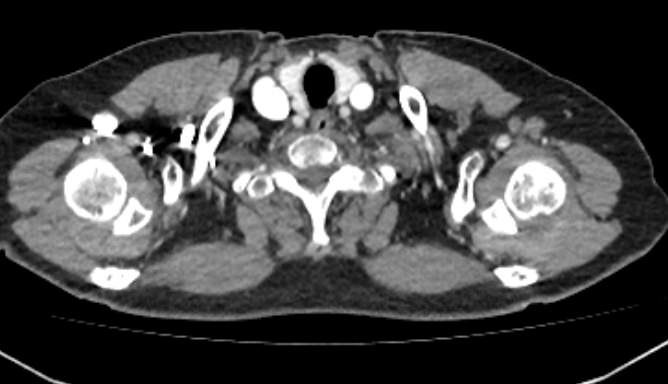

Мультиспиральная компьютерная томография является современным лучевым методом исследования, который позволяет с помощью рентгеновского излучения получить посрезовые снимки и после цифровой обработки создать объемные модели исследуемой области в мельчайших подробностях. Рентгеновские лучи в большей степени поглощаются плотными тканями организма, поэтому на снимках хорошо визуализируются кости скелета. Для оценки состояния мягкотканных структур в обязательном порядке проводится контрастное усиление.

Введение контраста требуется для лучшей визуализации мягких тканей конечностей, включая мышцы, связки, лимфатические узлы, нервные стволы и сосудистую систему и назначается для выявления воспалительных процессов, сосудистой патологии, при подозрении на опухолевые образования.

Йодсодержащий контрастный препарат вводится внутривенно, после чего он хорошо окрашивает кровеносные сосуды. Так как патологические очаги, и особенно опухолевые образования, имеют развитую сосудистую сеть, за счет этого они отчетливо контрастируют на фоне здоровых тканей. Методика контрастирования позволяет проводить точную и достоверную диагностику патологических процессов мягких тканей конечностей, включая опухоли на ранних стадиях развития, когда значительно выше шансы пациента получить эффективное лечение.

В наших медицинских центрах КТ верхней конечности с контрастом выполняется на современных мультиспиральных компьютерных томографах экспертного уровня TOSHIBA AQUILION. Аппараты послойно сканируют область исследования, одномоментно выполняя множество тончайших срезов. В результате получаются снимки высокого качества и трехмерные модели с изображением костного скелета и мягких тканей конечностей. При этом методика скоростного мультисрезового сканирования обеспечивает минимальную дозу рентгеновского облучения для пациента.